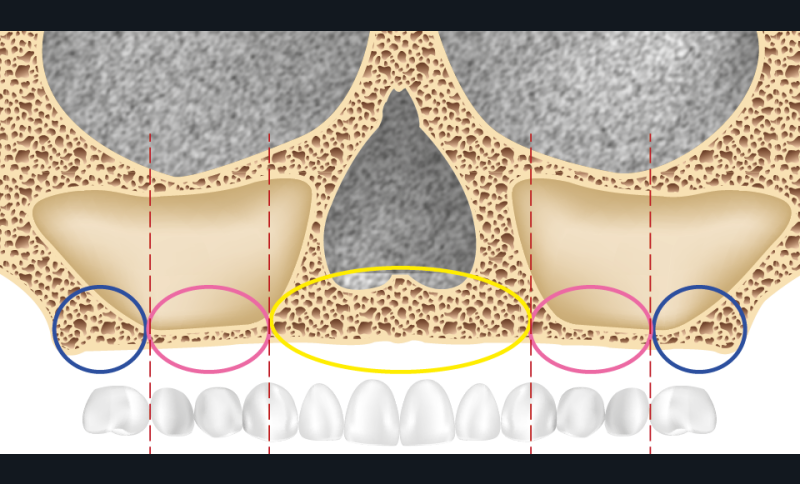

La perte des dents s’accompagne toujours d’une résorption osseuse plus ou moins importante, phénomène parfois accentué par le port de prothèses amovibles qui peuvent se révéler iatrogènes et accroître la perte osseuse. La classification de Bedrossian [1] divise le maxillaire supérieur en trois zones (fig. 1) :

- zone 1 : sous-nasale ;

- zone 2 : bosse canine (comprise entre les fosses nasales et le mur antérieur des sinus) ;

- zone 3 : sous-sinusienne.

La présence d’os dans les trois zones autorise une distribution idéale des implants avec notamment l’absence de cantilever. Quand l’os est absent ou en faible quantité dans la zone 3, le recours à l’angulation des implants distaux le long du mur antérieur des sinus est possible ; le cas peut alors être traité selon la technique « All-on-four ». En revanche, quand le seul volume osseux disponible est en zone 1, le recours à des implants transzygomatiques (ou à des greffes osseuses) est indispensable [2].